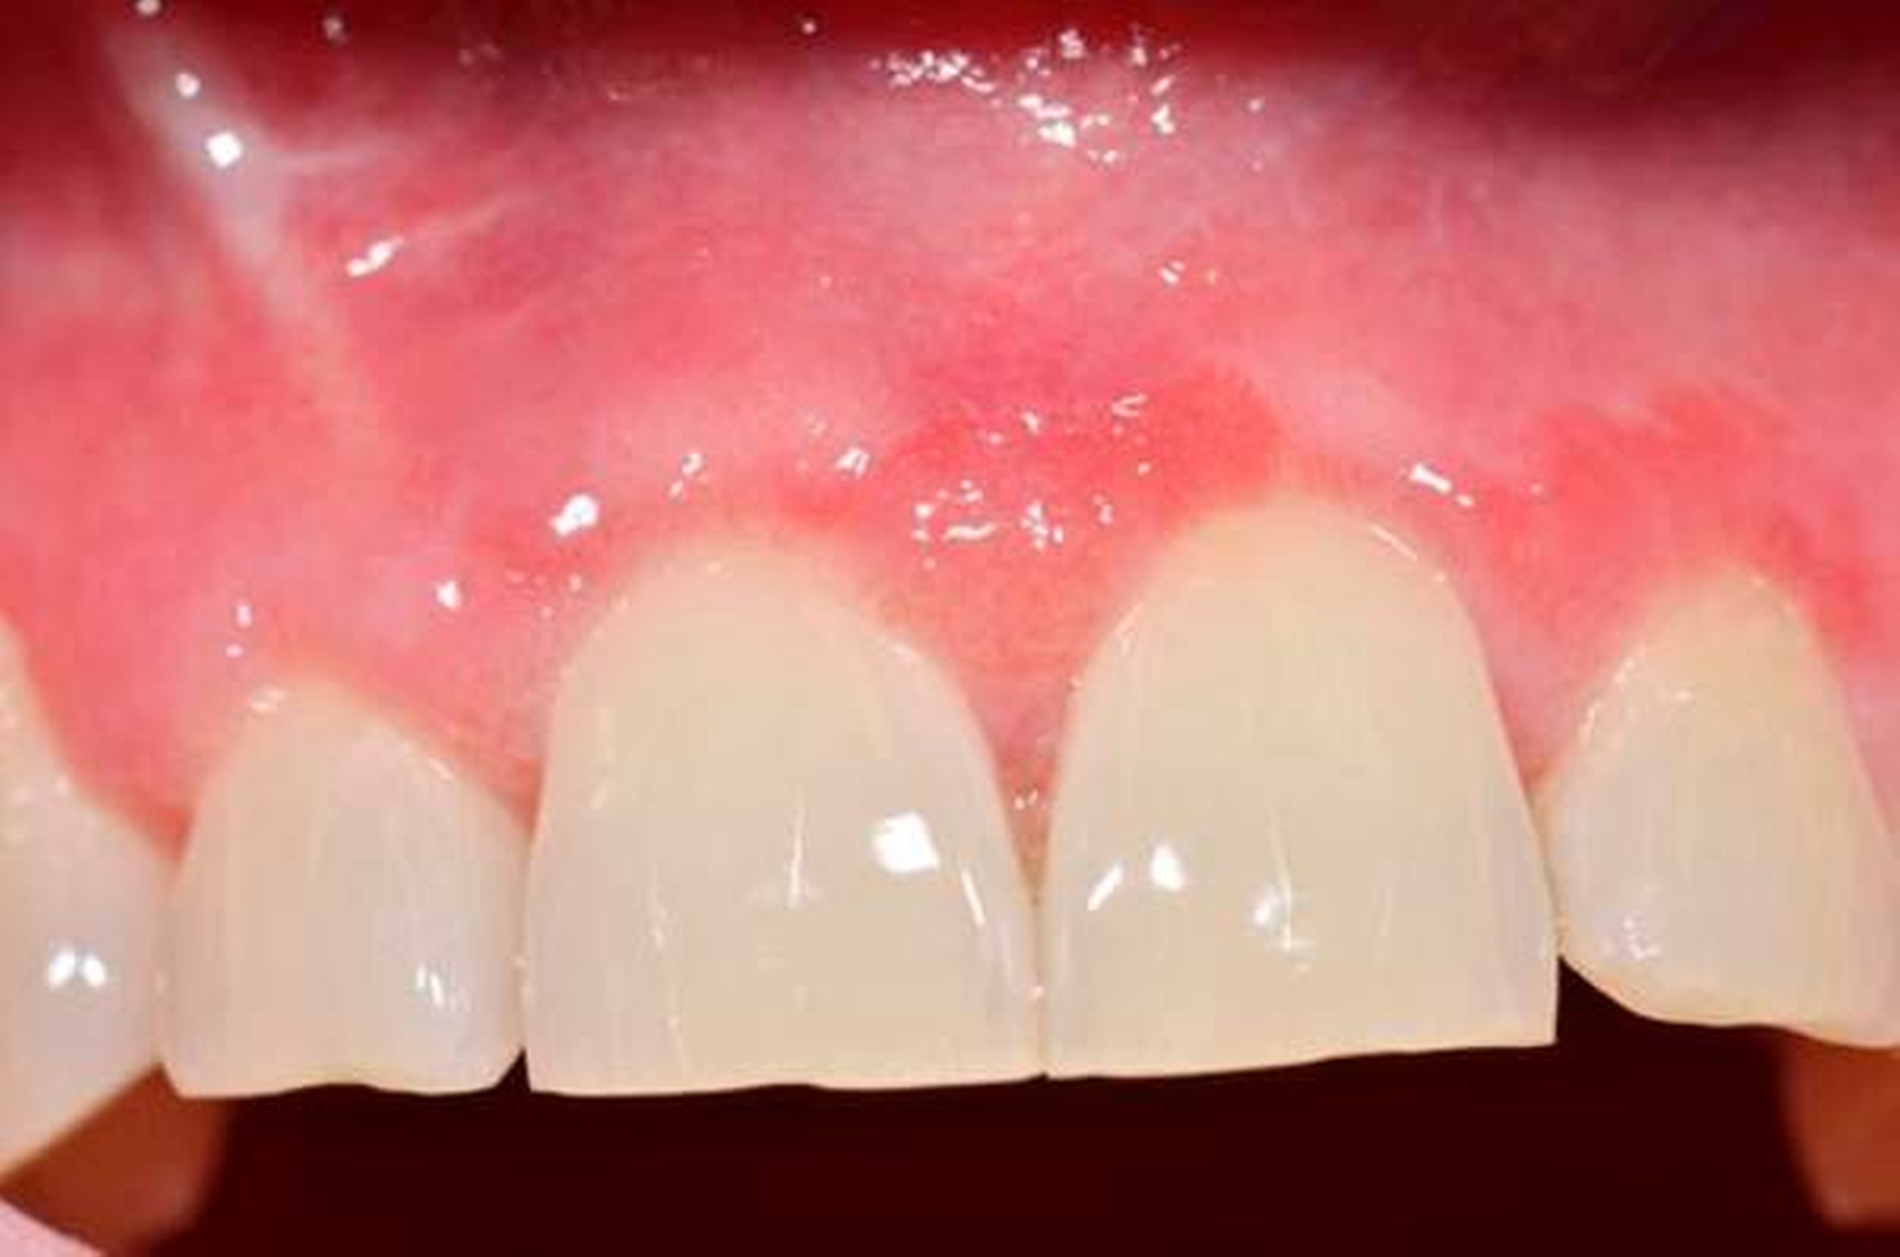

Die Therapie bestand daher initial nach Abschluss der Wundheilung aus lokalen Steroiden zunächst als Applikation von Triamcinolonacetonid (Volon-A-Haftsalbe) sowie einer begleitenden antimykotischen Therapie mit Amphotericin-B-Lutschtabletten (Ampho Moronal; 3 x d). Bei fehlender Wirksamkeit der Haftsalbe erfolgte bei einem Nachsorgeintervall von zwei Monaten die Umstellung auf ein höherpotentes Glukokortikoid (Clobetasol). Unter dieser Medikation zeigte sich ein schneller Rückgang der Beschwerden und der oralen Manifestation des Morbus Crohn (Abbildung 3).

Der Morbus Crohn ist eine chronisch-entzündliche Erkrankung, die den gesamten Gastrointestinaltrakt inklusive der oralen Mukosa betreffen kann. Die krankheitsspezifischen Manifestationen im Mund, die in 8 bis 29 Prozent aller Fälle auftreten [Pereira und Munerato, 2016; Jose et al., 2009], schließen unter anderem granulomatöse Entzündungen mit orofazialen Schwellungen, eine granulomatöse Cheilitis, hyperplastische Areale, oberflächliche und tiefe Ulzerationen (Abbildung 4) und apthöse Läsionen (Abbildung 5) sowie Gingivitiden – wie auch im vorgestellten Fall – ein [Miest et al., 2016]. In 5 bis 10 Prozent aller Morbus-Crohn-Fälle wird davon ausgegangen, dass die oralen Läsionen vor der gastrointestinalen Beteiligung entstehen [Jose et al., 2009]. Die Läsionen können direkt mit dem zugrundeliegenden Krankheitsprozess in Verbindung stehen oder sekundär kausal aufgrund des Ernährungsmangels durch die gastrointestinale Malabsorption entstehen [O‘Neill und Scully, 2012]. Im vorliegenden Fall entstand die Verdachtsdiagnose vor allem aufgrund des bereits vordiagnostizierten Morbus Crohn.